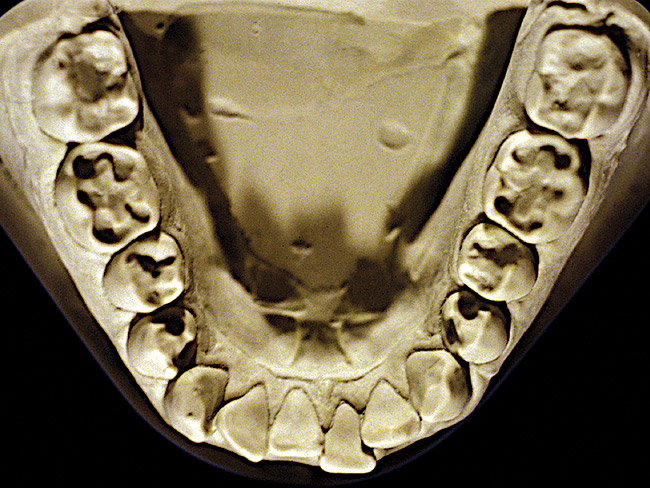

The patient shown in Figure 3 and Figure 4 exhibited severe NCLTS from bruxism. Examination of the casts indicated that the NCLTS was progressively greater toward the anterior teeth. Cupping and cratering was not present because there was no secondary cause. Figure 5 and Figure 6 detail another bruxism patient, but to a lesser degree and one with cupping/cratering caused by toothpaste. The cups or craters were not caused from bruxism because the teeth could not touch the bottom of the invaginations. In both featured patients, upon hand-articulating the casts, the NCLTS facets matched up and the diagnosis of bruxism was confirmed.

Figure 8  Moderate NCLTS from toothpaste, mandibular arch.

Figure 8